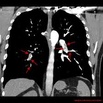

Zator tętnicy płucnej jest główną przyczyną chorobowości I śmiertelności wśród chorych poddawanych zabiegom kardiochirurgicznym w trybie pilnym, z całkowitą śmiertelnością wahającą się od 6% do aż 85%. Choć leczeniem pierwszego rzutu jest postępowanie niechirurgiczne lub interwencja przezskórna, to u chorych we wstrząsie kardiogennym leczenie operacyjne ciągle pozostaje metodą z wyboru. Nasz ośrodek regularnie wykonuje operacje embolektomii tętnicy płucnej, których rezultat jest lepszy, niż podają aktualne doniesienia. W związku z tym przeprowadziliśmy retrospektywną analizę wyników leczenia chorych z zatorem tętnicy płucnej i rodzaju anestetyków stosowanych podczas leczenia.